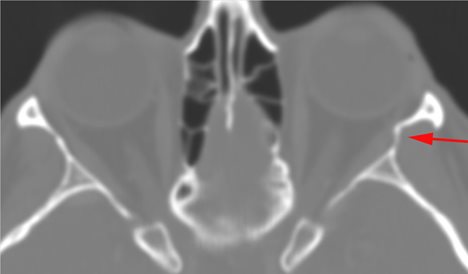

Orbits and Orbital Zygomatic Complex

There is evidence of bony injury along the walls and/or floor of the orbit.

The supraorbital and infraorbital rims and orbital process of the zygoma and/or frontozygomatic suture are fractured.

The zygomatic arch is fractured.